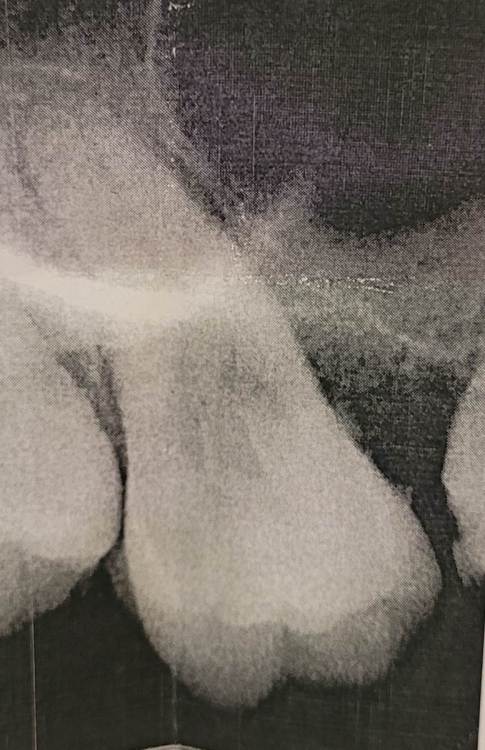

Валерия0309 Опубликовано 17 июля, 2023 Поделиться Опубликовано 17 июля, 2023 Добрый день. Несколько месяцев болит зуб (7 сверху справа). На первом приеме врач ничего не нашел и решил, что это я повредила десну ирригатором. Все это время мазала десну. Но боль не проходила. На втором приеме оказалось, что зуб опустился вниз и слегка подвижный. Сказали, что пародонтит и где-то глубоко кариес и отправили на удаление. Нужно ли его удалять или можно спасти? Ссылка на комментарий

IvanK Опубликовано 19 июля, 2023 Поделиться Опубликовано 19 июля, 2023 Добрый день по данному снимку показаний к удалению не вижу я бы советовал сделать компьютерную томографию, послушать еще одно мнение Ссылка на комментарий